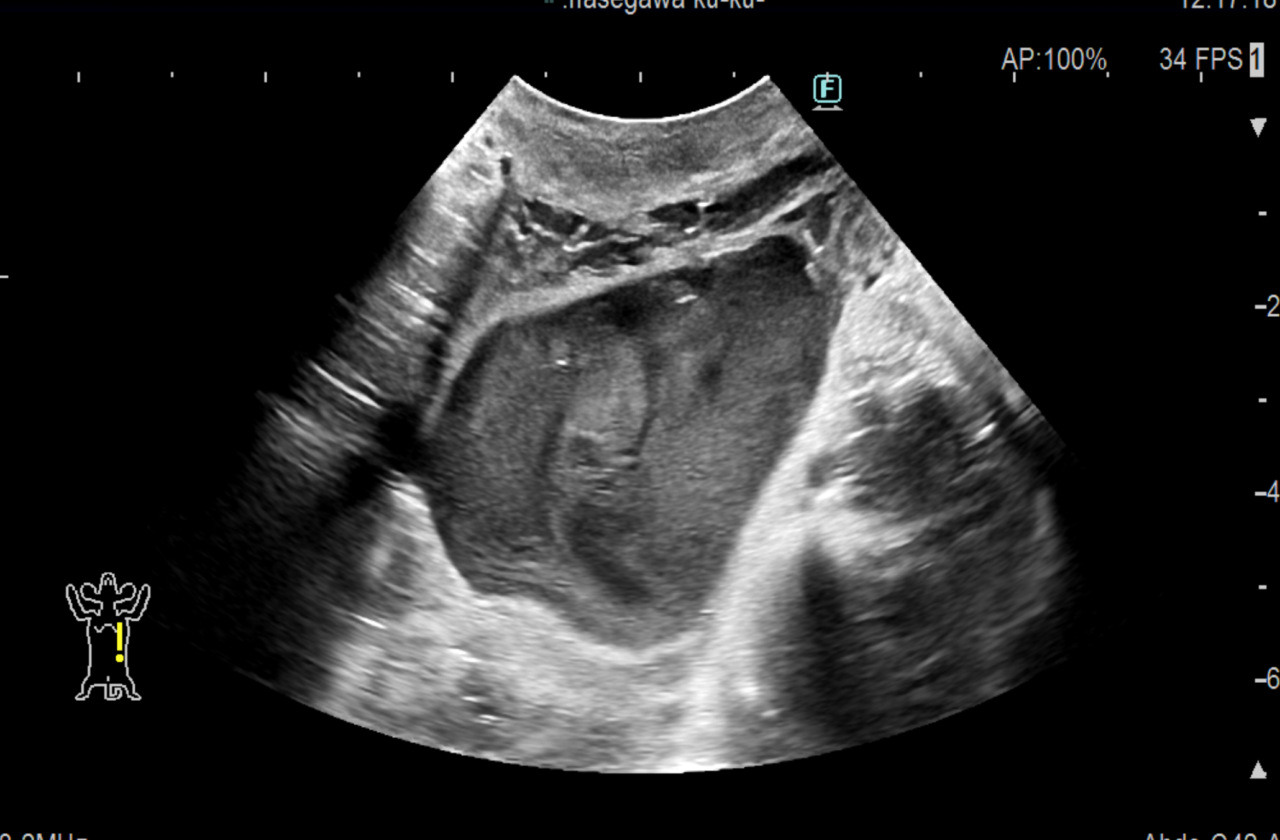

腹部超音波検査では前立腺実質エコーは均質であり、形状は通常左右対称である。前立腺炎の場合、実質は不均一であり、多巣性の低エコー領域が存在する。前立腺膿瘍および前立腺内嚢胞は局所的な単一または複数の無から低エコーの構造として現れる。